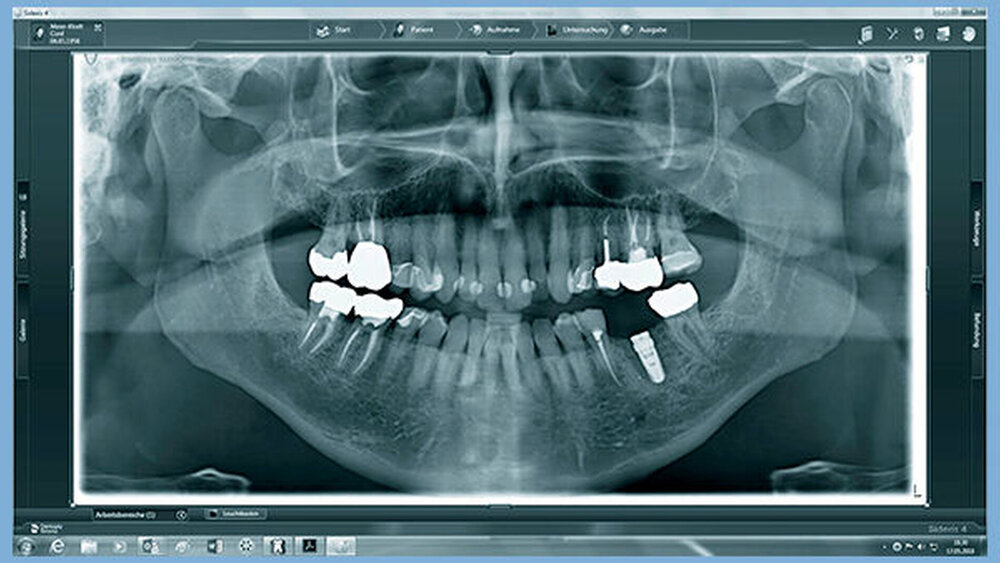

Ruppin:

Zu den Standardfehlern gehört auch, das Ausmaß von notwendigem Knochenaufbau zu unterschätzen. Es wird nicht konsequent genug bzw. gar nicht augmentiert. Die Implantate stehen dann zu weit oral und in der Achse zu weit nach bukkal. Die Möglichkeiten für prothetischen Ausgleich sind dabei auch sehr begrenzt. Ohne ein konsequentes Backward Planning ist Implantologie gerade in komplexeren Fällen heute als fahrlässig anzusehen!